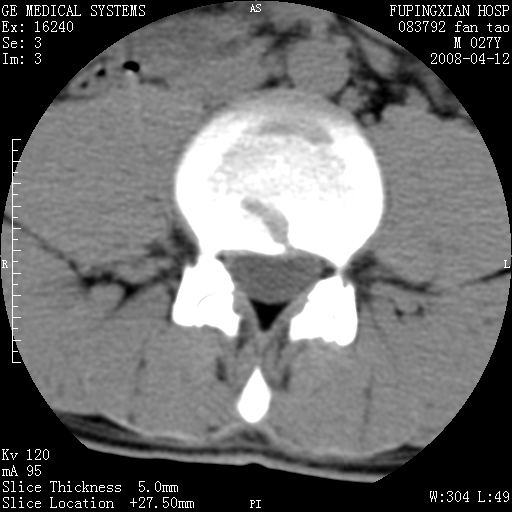

以下是引用前行在2008-4-13 13:53:00的发言:[br]椎间盘髓核终板下突出形成许莫氏结节及椎间盘突出,建议mr检查

以下是引用xclzq_910在2008-4-13 12:43:00的发言:[br]这个应该没什么了,椎间盘突出后反应性骨质吸收硬化.建议mr